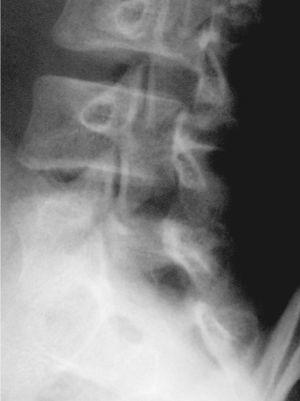

En la visita siguiente el paciente se presenta con radiografías que confirman el diagnóstico de espondilólisis L5 unilateral derecha (figs. 2 y 3). De acuerdo con el Documento de Consenso de la Societat Catalana de Medicina de l'Esport, se solicita una gammagrafía ósea planar (GOP) con tomografía computarizada por emisión de fotón simple (SPECT). Se decide continuar con el mismo tratamiento y se informa al paciente que será un tratamiento a largo plazo.

Figura 2

Figura 3